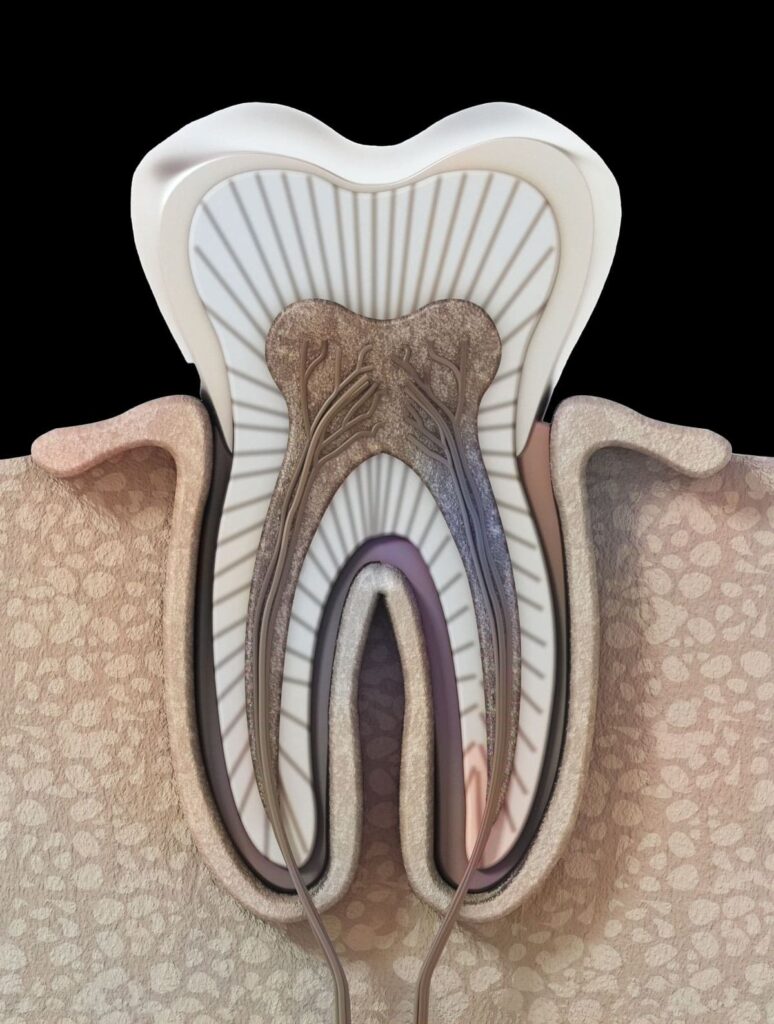

Dişler insan vücudunda bulunan en sert yapıya sahiptirler. (1) Çiğnemek ve konuşmak için oldukça önemli bir işleve sahip olan dişler 5 bölümde incelenir.

- Mine: Dişin en dış kısmıdır aynı zamanda en sert kısmı olarak da ifade edilebilir. Mine kaya gibi sert olması ile bilinen bir mineral olan kalsiyum fosfattan oluşur.

- Dentin: Minenin altındaki tabakaya bu ad verilmiştir. Dentin tabakası da sert bir dokuya sahiptir, bu tabaka mikroskobik tüpler içerir. Mine zarar gördüğünde, aşındığında ısı bu yollardan dişe girer. Sıcak ya da soğuk hassasiyeti minenin aşınması ve ısının dentinde bulunan mikroskobik tüplere ulaşması ile ortaya çıkar.

- Pulpa (Dişözü): Dişin yumuşak iç yapısı pulpadır. Kan damarları ve sinirler pulpada bulunur.

- Sementum: Diş köklerini diş etlerine ve çene kemiğine bağlayan bağ dokusu tabakasıdır.

- Periodontal Ligament: Dişlerin çeneye sıkıca tutunmasına yarımcı olan dokudur. (2)

Diş kanalları, pulpada başlayan ve kök kısmına doğru inen kanallardır. Kanal tedavisi de bu kanalların temizlenmesi esasına dayanılarak yapılır. Kök kanalları olarak da adlandırılan bu yapılar pulpada yer alır. Diş minesi ve dentinde meydana gelen bir hasar pulpanın ve kök kanallarının enfekte olmasına, iltihaplanmasına, derin çürümeye bağlı hasar almasına hatta pulpanın nekzoruna yani ölmesine neden olur.

Kanal tedavisi çürümüş, iltihaplanmış veya enfekte olmuş bir dişi onarmak ve kurtarmak için kullanılan bir tedavidir. Dişteki pulpa ve sinirler çürüme sebebiyle tahriş olabilir, iltihaplanabilir, ölebilir veya enfekte olabilir. Dişin iç kısmının etkilenmesinin temel nedenleri çürümenin derinleşmesi, diş minesinde çatlak veya kırık olması, yüze alınan bir travma sebebiyle dişte hasar meydana gelmesi olarak ifade edilebilir. (4)

anal tedavisi iltihaplanan, enfekte olan kök kanalındaki bakterileri yok etmek ve dişin yeniden enfeksiyon yapmasını engellemek, doğal dişi korumak için yapılan bir tedavi yöntemidir. Kanal tedavisinde süreç kök kanalına girilmesi, enfekte olan pulpanın çıkarılması ve dişin iç kısmının dikkatlice temizlenip dezenfekte edilmesi işlemleri ile ilerler. Son olarak diş doldurulur ve yeniden enfekte olmaması için mühürlenir.